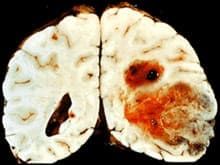

Исследование вакцины проводилось на 120 пациентах с глиобластомой. Это одна из наиболее агрессивных форм рака мозга.

До 98% больных умирают в течение пяти лет после постановки диагноза. Для лечения, как правило, используется лучевая и химиотерапии, а также хирургическое лечение, но в целом болезнь неизлечима.